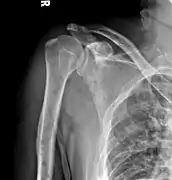

The diagnostic examination of a person with suspected multiple myeloma typically includes a skeletal survey. This is a series of X-rays of the skull, axial skeleton, and proximal long bones. Myeloma activity sometimes appears as "lytic lesions" (with local disappearance of normal bone due to resorption) or as "punched-out lesions" on the skull X-ray ("raindrop skull"). Lesions may also be sclerotic, which is seen as radiodense.[70] Overall, the radiodensity of myeloma is between −30 and 120 Hounsfield units (HU).[71] Magnetic resonance imaging is more sensitive than simple X-rays in the detection of lytic lesions, and may supersede a skeletal survey, especially when vertebral disease is suspected. Occasionally, a CT scan is performed to measure the size of soft-tissue plasmacytomas. Bone scans are typically not of any additional value in the workup of people with myeloma (no new bone formation; lytic lesions not well visualized on bone scan).

X-ray of the forearm, with lytic lesions

Multiple myeloma in the upper arm